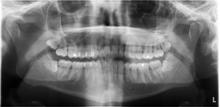

Et besøg hos tandlægen i slutningen af November 2014 viser, at det